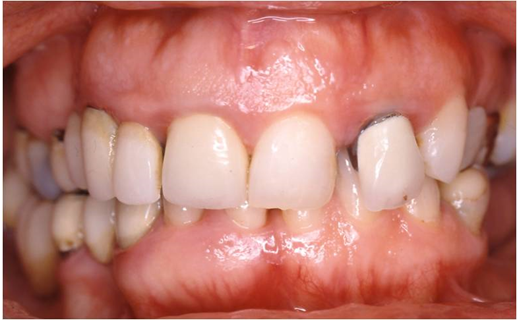

3. Ελκονεκρωτική ουλίτιδα σε έδαφος περιοδοντίτιδας

Η ασθενής ετών 29 προσήλθε στο ιατρείο μας παραπονούμενη για αυτόματη αιμορραγία και έντονο πόνο στα ούλα, αδυναμία βουρτσίσματος και μεγάλη δυσοσμία στόματος. Στην κλινική εξέταση παρατηρήθηκαν έλκη και απώλεια των μεσοδοντίων θηλών, ιδιαίτερα στα πρόσθια δόντια, καθώς και μεγάλη παρουσία μικροβιακού παράγοντα. Παράλληλα, κατά την ακτινολογική εξέταση διαπιστώθηκε οστική απώλεια ιδιαίτερα στα πρόσθια δόντια της κάτω γνάθου και στα οπίσθια άνω και κάτω γνάθου.

ΕΛΚΟΝΕΚΡΩΤΙΚΗ ΟΥΛΙΤΙΔΑ - ΑΡΧΙΚΗ ΚΑΤΑΣΤΑΣΗ